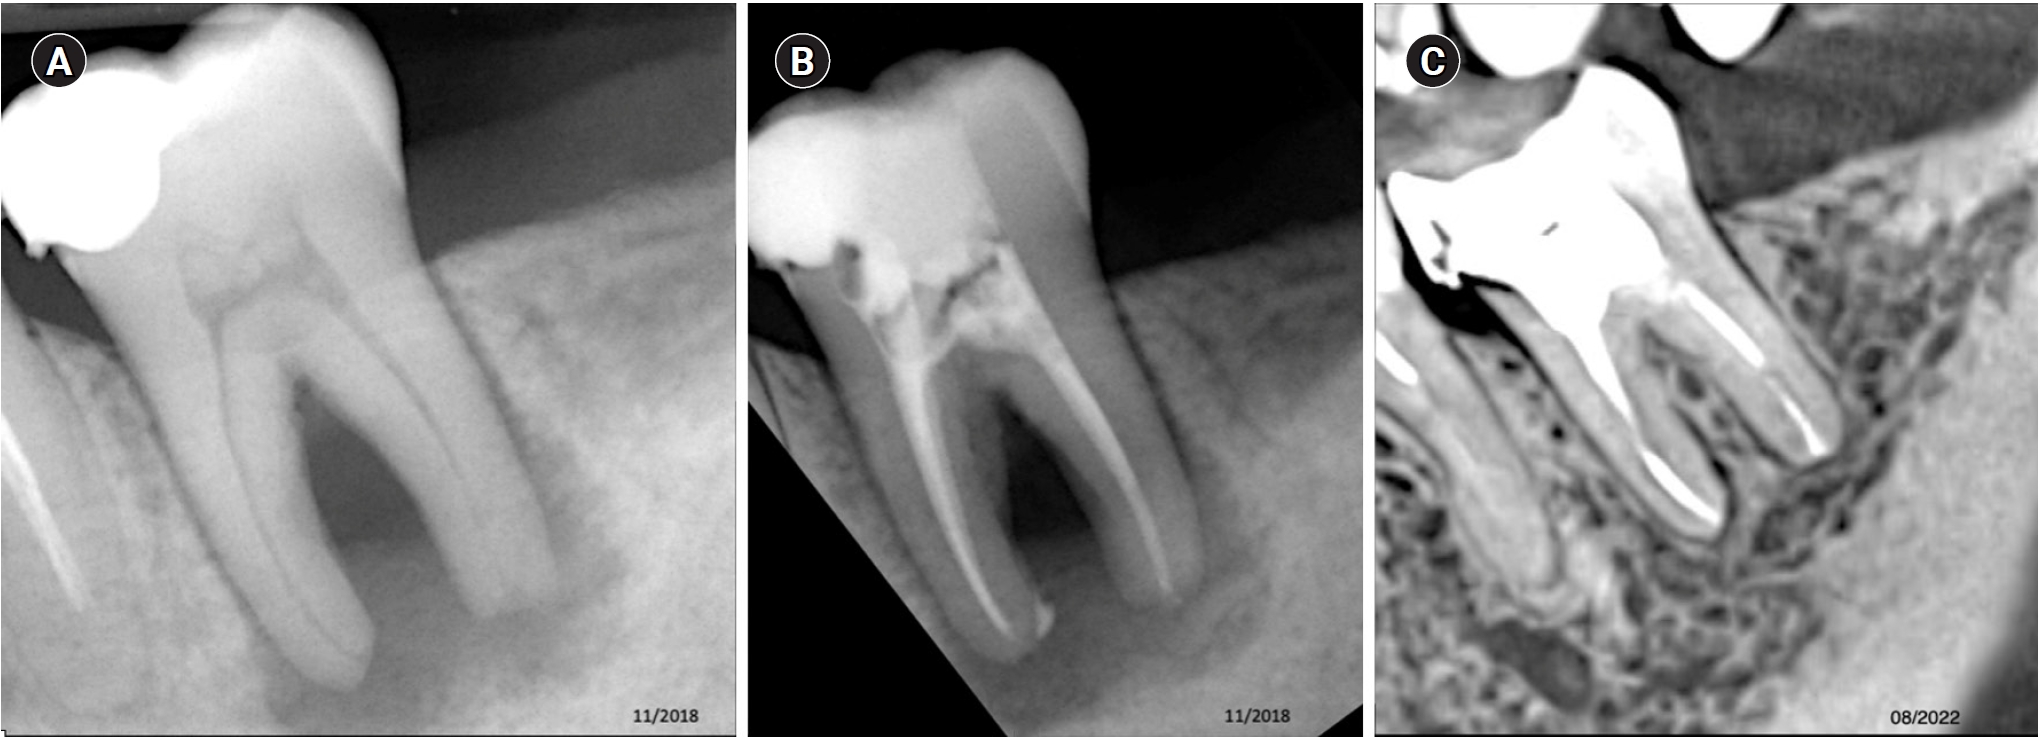

- Cone-beam computed tomography in endodontics: from the specific technical considerations of acquisition parameters and interpretation to advanced clinical applications18

- Cone-beam computed tomography in endodontics: from the specific technical considerations of acquisition parameters and interpretation to advanced clinical applications3,348